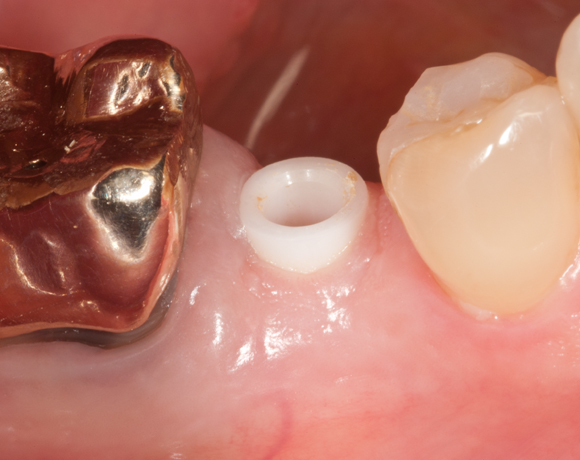

Offene Abdrucknahme bedeutet, dass beim Abformen ein Abdrucklöffel benutzt wird, bei dem über dem Implantat vorab ein loch gebohrt wird, durch das die Schraube des Abdruckpfostens herausragt und nach Aushärten des Abdruckmaterials abgezogen werden kann.

Bei diesem Patientenfall wird die offene Abdrucknahme gezeigt und die Herstellung einer Krone auf einen CAD/CAM Pfosten.